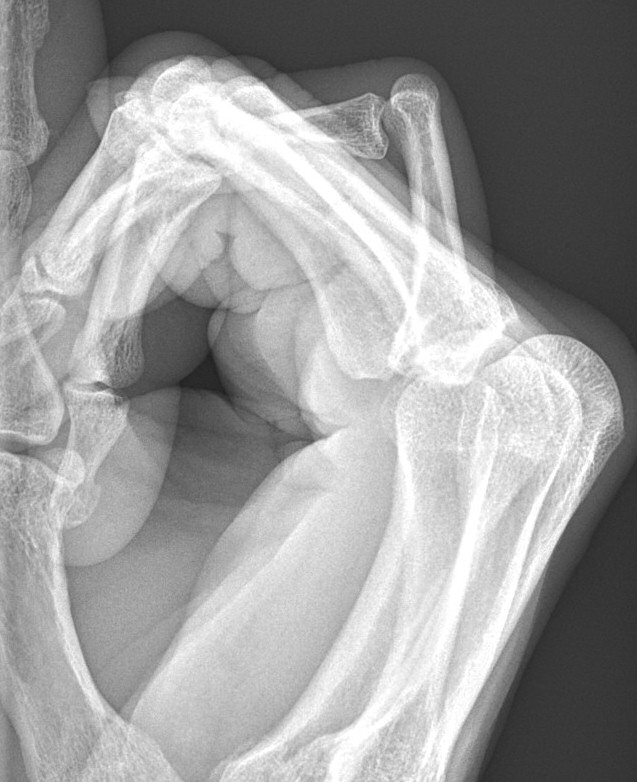

Volar luxation i PIP-led